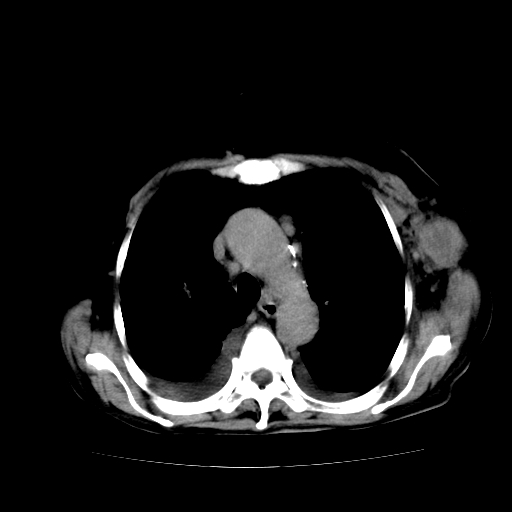

女70y乳腺ca(针吸活检)

多部位转移瘤的诊断可以肯定,我的疑问是:双肺对称高密度影及胸水是否为心衰肺水肿,病人体虚弱,不好意思图象传的乱![em9]

1)左侧乳腺癌并左侧腋窝及纵隔淋巴结转移,两肺淋巴道转移(癌性淋巴管炎),肝脏多发性转移。2)双侧胸腔积液。3)慢性胆囊炎。

1)左侧乳腺癌并左侧腋窝及纵隔淋巴结转移,肝脏多发性转移。2)双侧胸腔积液伴双肺蝶翼样磨玻璃高密度影,双侧肺门血管影增粗(图像不全,肺门层面没纵隔窗),考虑心功能不全所致。3)慢性胆囊炎伴壁钙化。